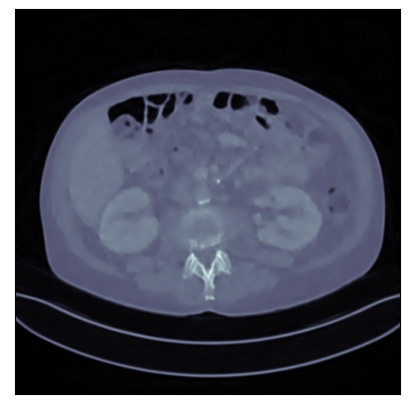

Refer to captionRefer to caption

Ground-truth

FBP: 21.303 dB, 0.195

TV: 31.690 dB, 0.889

U-Net: 36.712 dB, 0.920

LPD: 36.810 dB, 0.912

AR: 36.694 dB, 0.907

ACR: 35.708 dB, 0.897

ACNCR: 36.533 dB, 0.921

AWCR: 37.603 dB, 0.918

AWCR-PD: 37.941 dB, 0.924

Figure 2: Reconstructed images obtained using different methods, along with the associated PSNR and SSIM, for sparse view CT. In this case the AWCR and AWCR-PD achieve the highest PSNR and SSIM. Furthermore, both AWCR methods retain the fine-structure in the reconstruction, unlike the ACNCR and ACR, the only other methods which possess convergence guarantees.

Limited view CT In this setting a specific angular region contains no measurement, turning this into a severely ill-posed inverse problem, and a good image prior is crucial for reconstruction. As shown in [Mukherjee et al., 2021], the AR begins introducing artifacts during reconstruction, which is overcome for both the ACNCR and ACR due to the imposed convexity. The AWCR, on the other hand, is able to remain non-convex without experiencing deterioration. However, the AWCR-PD method performs worse in this setting, though still outperforming AR. This occurs due to the forward and the adjoint operator being severely ill-posed. For a visual comparison of the AWCR and AWCR-PD methods in this setting, see Section G.2.